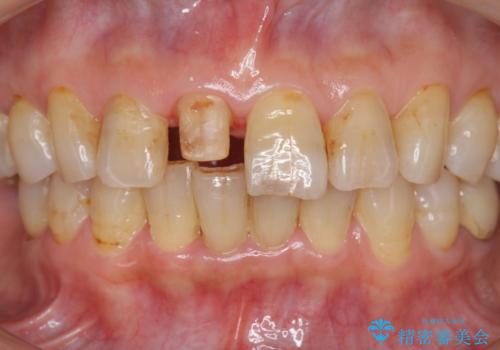

- 前歯を転倒で受傷し、審美性の回復を求めて来院されました。

近医で暫間的なコンポジットレジン修復が為されていましたが、色調に不満があるということでした。

色調の変化が少なく、長期的な予後を見込めるジルコニアクラウンで天然歯を模した審美性の回復を計画します。